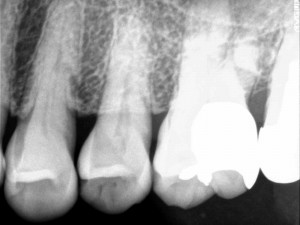

健康な骨

健康な骨であれば、歯を十分に支えることができるため、揺れて抜け落ちてしまうこともありません。しかし歯周病が進んでいくと、歯の周りの骨が溶けて歯を支えることができなくなってしまうため、歯が揺れてきて、ついには抜け落ちてしまいます。